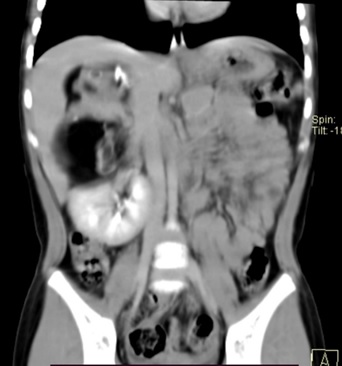

Teratoma maduro retroperitoneal en un infante, una entidad poco frecuente. A propósito de un caso

Jorge Aurelio Gutierrez Gonzalez, Anya Yamilia Adame Gutiérrez, Luis Tamez Pedroza, Edmundo Martínez Garza, José Guillermo Martínez Flores, Fernando Félix Montes Tapia, Gerardo Enrique Muñoz Maldonado

101-105